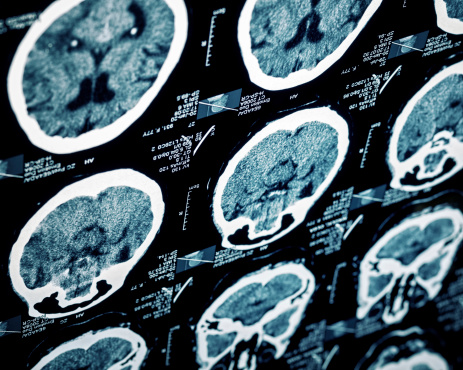

A hypertension drug has been shown to block traumatic brain injury (TBI) inflammations caused by liver proteins. TBI has been shown to affect the body as well as the brain in animal studies. The findings were discovered by researchers at Georgetown University Medical Center.

Researchers found that brain injuries produce an inflammatory response, in particular within the liver. In return, the liver boosts protein production which increases inflammation in the brain, contributing to chronic inflammation, nerve cell death and reduction in blood flow.

In mice models, the researchers found that using a drug to treat hypertension blocks the production of a particular molecular which can reduce inflammation. When this molecule is blocked it allows the brain to better heal. Researchers report that 1.7 million-plus people experience a TBI annually, and uncovering a treatment could greatly improve their health.